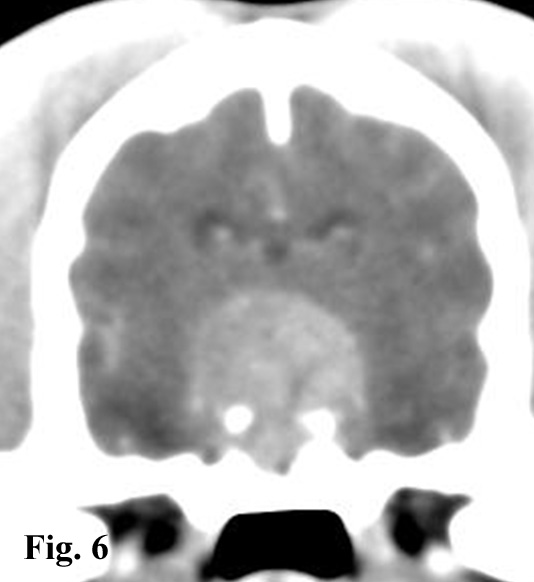

Video 1:Cane meticcio femmina di 9 anni con ipercortisolismo ipofisi dipendente e miotonia agli arti posteriori. Si noti l’andatura del tipo “bunny hopping” dovuta all’estrema rigidità degli arti posteriori.Video 2: Cane Beagle maschio di 12 anni affetto da ipercortisolismo ipofisi dipendente. Si noti l’andatura compulsiva del soggetto. La tomografia computerizzata ha messo in evidenza la presenza un macroadenoma ipofisario (Fig. 6)

Sintomatologia nervosa: nei soggetti affetti da un macroadenoma ipofisario la compressione sulle strutture circostanti può determinare una sintomatologia nervosa caratterizzata da alterazioni dello stato mentale (ottundimento del sensorio, stupor), atassia, tetraparesi, disorientamento e soprattutto compulsione (Fig. 6) (Video 2) .

I tumori di grandi dimensioni si individuano facilmente in immagini TC con mezzo di contrasto, per la loro grandezza e per la loro forma alterata (Fig. 6), mentre a volte possono essere difficili da visualizzare senza mezzo di contrasto. Nel 50-60% dei cani con ipercortisolismo ipofisario, si può individuare una massa ipofisaria tramite TC; nel rimanente 40-50% dei casi, la patologia è causata da un microadenoma di dimensioni inferiori a 3-4 mm, che non è visibile neanche con contrasto.